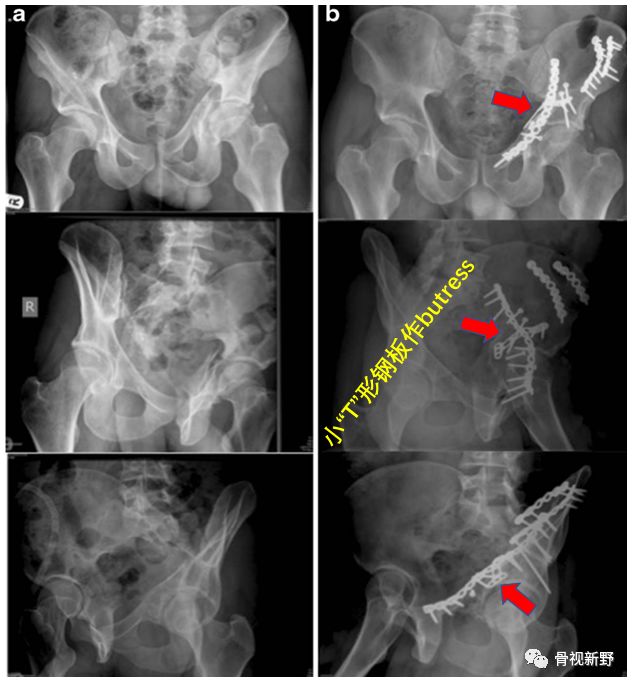

髋臼骨折的防滑、支撑固定

四边体骨折的buttress固定

小“T”形钢板作四边体的buttress固定

LC-DCP作四边体的buttress固定(Int Orthop. 2015;39(11):2219-26)

髋臼后柱骨折的buttress固定

通过髂腹股沟单一切口同时行前柱ORIF及后柱内侧壁的buttress钢板固定(Int Orthop. 2017;41(1):165-171)。